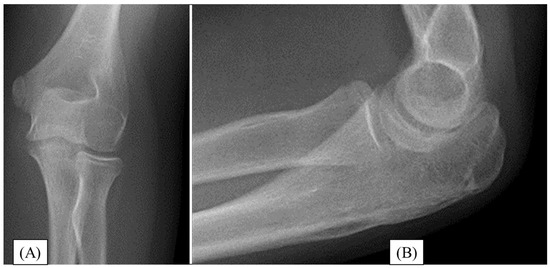

3.3. Case 3